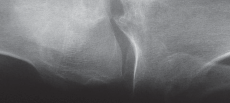

الأشعة السينية العادية (Plain Radiographs):

- المنظر الأمامي الخلفي (AP): يُظهر الركبة من الأمام.

- المنظر الجانبي (Lateral): يُظهر الركبة من الجانب.

- المنظر الخلفي الأمامي المثني (PA Flexed): يسمح بتقييم أفضل للجزء الخلفي من الركبة وقد يكشف عن تغيرات أكبر في الحجرة الخلفية الوحشية.

- منظر شروق الشمس (Sunrise/Patellofemoral): لتقييم المفصل الرضفي الفخذي.

- الأشعة السينية الطويلة للطرف السفلي بالكامل (Full-length standing radiographs): من الورك إلى الكاحل، وهي مفيدة جدًا، خاصة إذا تم استخدام تقنيات الملاحة الحاسوبية. تُظهر هذه الأشعة المحاذاة الكلية للطرف السفلي.